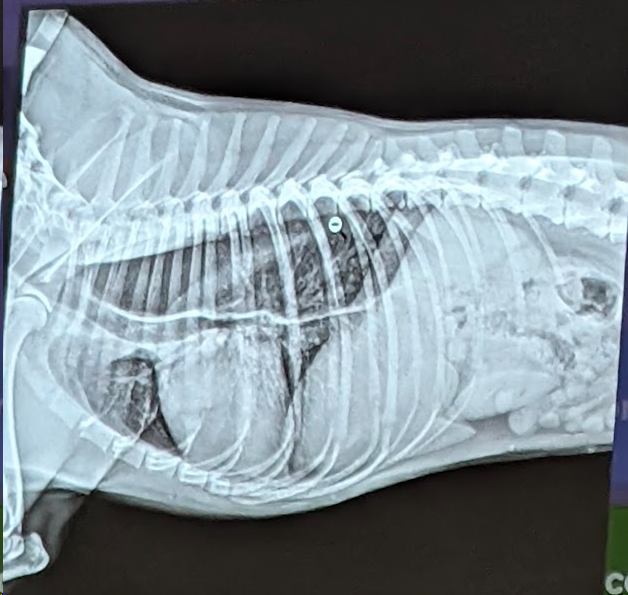

Preguna 6 - Multiple respuesta

- Hay un desplazamiento dorsal del piloro (por torsion estomacal)

- Signo de doble burbuja ( presencia de dos compartimentos llenos de gas en el estómago por el giro, el cual aparece distendido y rotado.)

- Torsión Gastrica

- Hay una dilatación gastrica (por torsión)